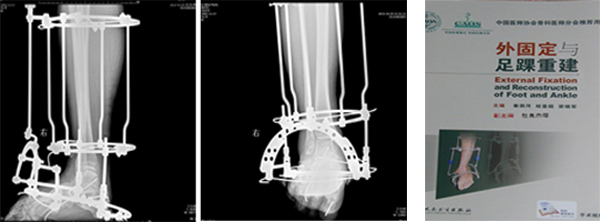

下肢畸形是脑、脊髓、周围神经等损伤后常见的并发症,严重影响患者生活质量,杜良杰教授带领团队开展了大量下肢矫形功能重建手术,使大量患者的站立和行走功能得到了显著提高。杜良杰主任作为副主编参与《外固定与足踝重建》的编写,该书成为中国医师协会骨科医师分会推荐用书。

脊髓损伤后下肢痉挛马蹄内翻足畸形矫形术后 杜良杰教授参编专著(副主编)